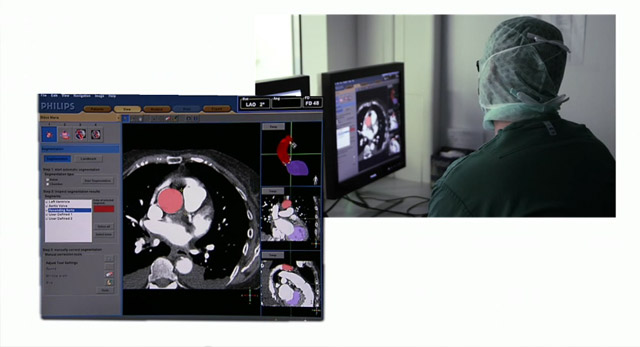

يتطلّب التعرّف الدقيق على هياكل القلب وفقًا للصور الطبية سنوات من التدريب والخبرة.

يمكن أن يشكل استخدام الأشعة السينية وتقنيات التصوير ثلاثي الأبعاد بالموجات فوق الصوتية وتفسيرها أثناء إجراءات علاج أمراض القلب الهيكلية (SHD) تحديًا، وخاصة عند توجيه مسابر القسطرة التي تحمل الأجسام المزروعة.

وبالتالي، يساعد الوصول السهل والسريع إلى الرؤية المحسنة والتنقل عبر المقاطع التشريحية للأنسجة الرخوة باستخدام التوجيه بالصور المباشرة في تحديد المسار الأمثل للعلاج بعد التوصل إلى التشخيص الصحيح الموثوق.